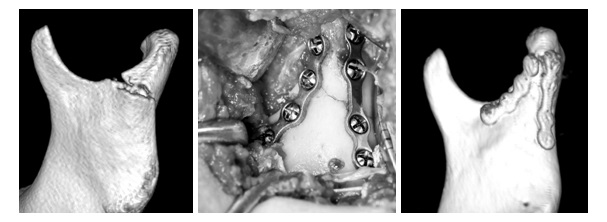

Wskaż prawdziwe stwierdzenie dotyczące przedstawionego złamania wyrostka kłykciowego:

Wskaż prawdziwe stwierdzenie dotyczące przedstawionego zespolenia

złamania wyrostka kłykciowego: